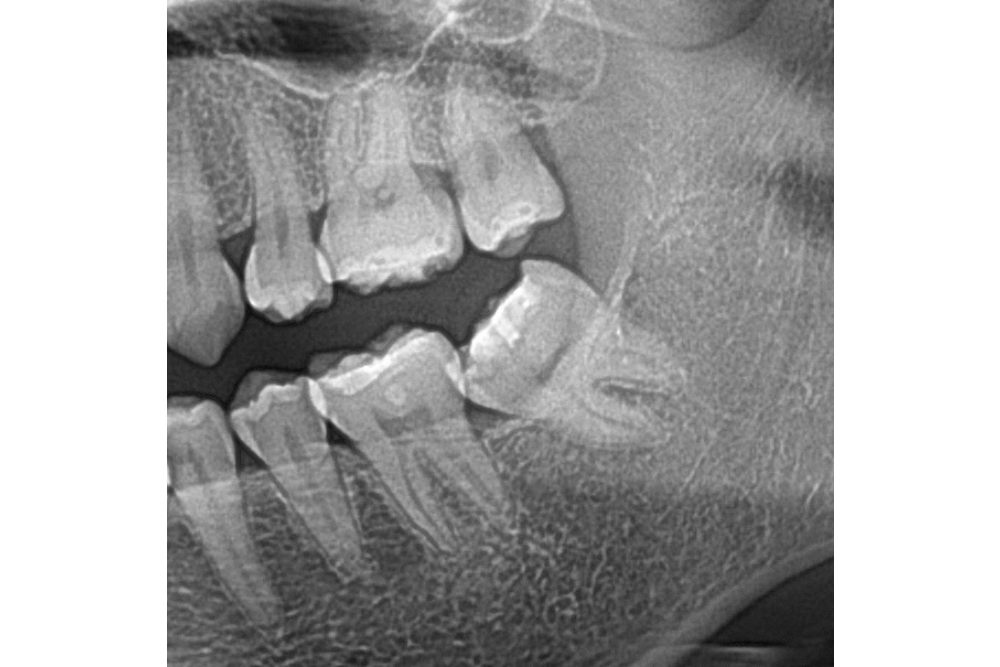

아래쪽 두 번째 어금니(제2대구치)가 선천적으로 없는 결손치로서, 사랑니(제3대구치)가 있으나 앞으로 쓰러져서 잘 안 씹히고 썩어 있습니다.

이런 경우 사랑니를 발치하고 임플란트를 하는 방법도 있으나, 본인 치아를 살리고 싶어하셔서 교정으로 접근하였습니다.

부분교정을 통해 누워있던 사랑니를 세웠으나, 씹는 면에 충치가 있습니다.

교정종료 후 보철치료(인레이)를 통해 씹는 기능을 회복시켰습니다.

누워있던 이가 세워져서 음식물이 더 잘 씹히게 되었습니다.

또한 음식물이 끼지 않게 되어 구강위생관리도 원활하게 되었습니다.